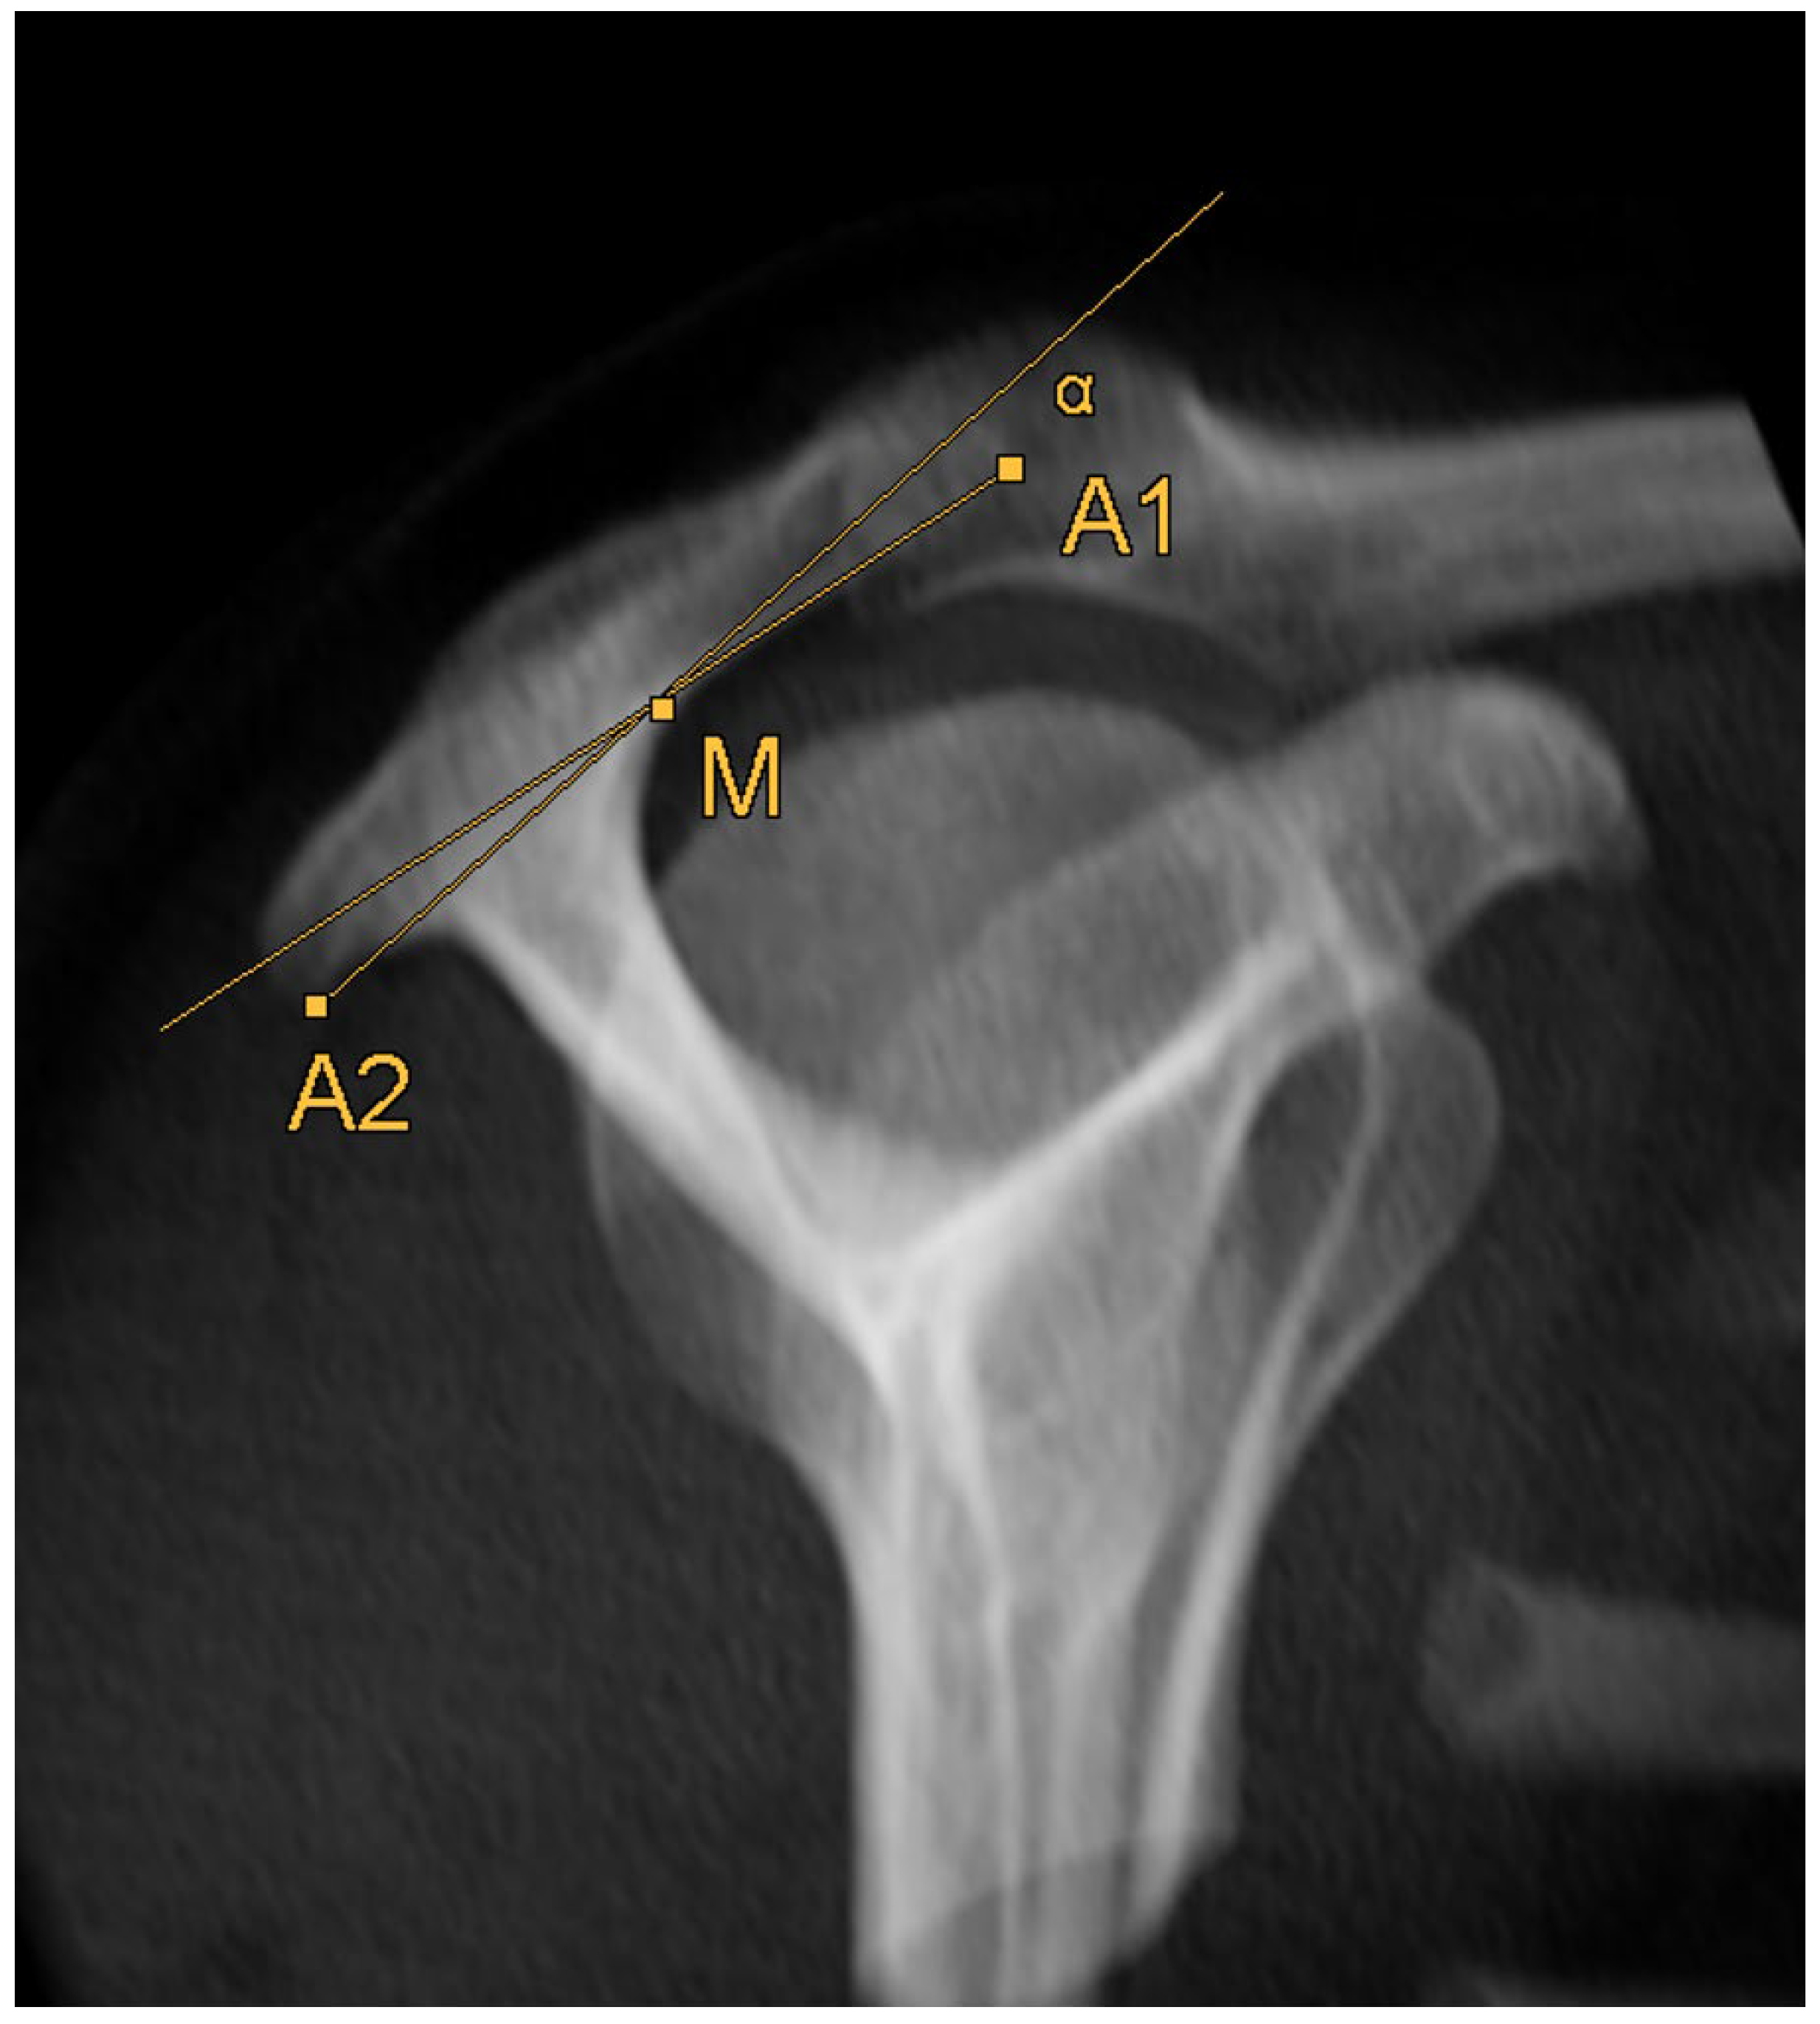

2.5. Acromion Slope (Figure 10)